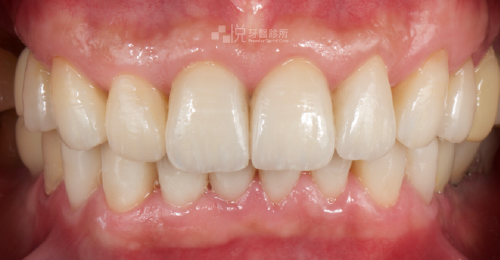

在品悅牙醫不只是幫患者解決當下的疼痛,更是透過詳細的全口評估找出問題的根本原因,包含徹底的檢查整體外觀、牙齒結構、牙周健康、咬合呈現等,進而規劃專屬於您的全口重建治療方針,使您恢復口腔健康、重現自信笑容。